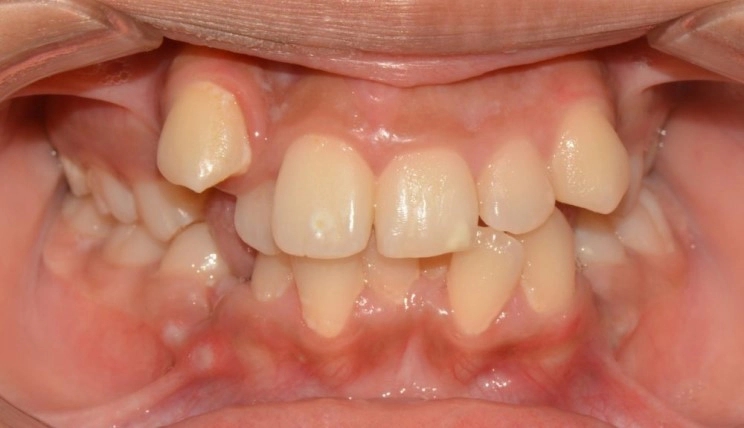

Chen chúc

Chen chúc là tình trạng có sự chênh lệch giữa kích thước răng và không gian có sẵn để sắp xếp răng trên cung răng.

Thông tin bệnh nhân:

Tuổi: 17

Giới tính: nữ

Lựa chọn điều trị Invisalign: Invisalign Comprehensive

Tổng thời gian điều trị:

29 tháng